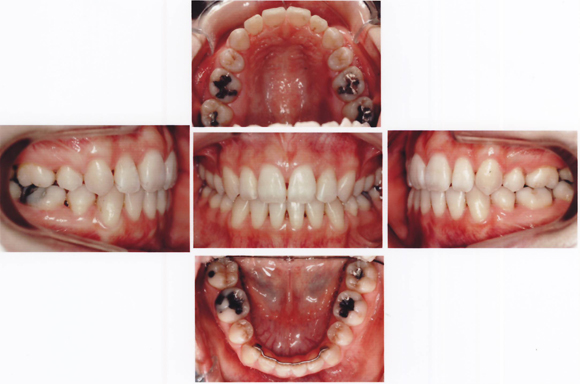

CASE4 乱杭歯(歯がひどく不揃いに生えている:八重歯や叢生も含む)ケース

![]()

術後